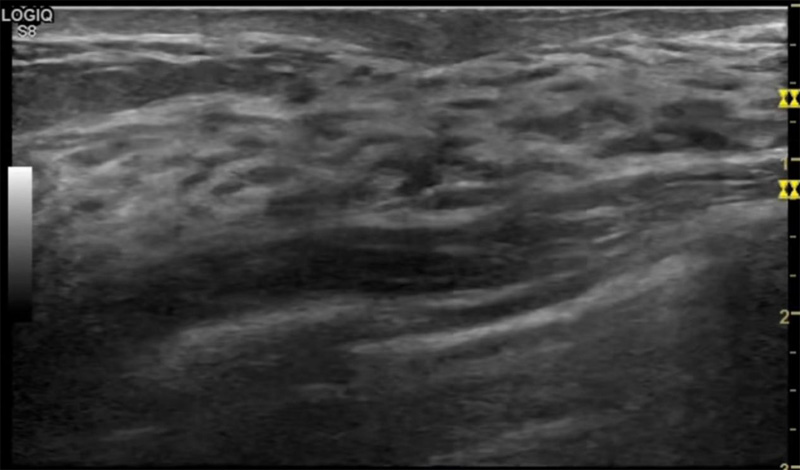

乳房胀痛,触摸疼痛,手摸起来感觉有肿块。这个是什么问题呢?医生诊断一般是乳腺增生。那么在乳腺超声设备检查后,报告单却显示双乳未见明显占位性病变。乳腺增生是很多女性,特别是育龄期女性都有的经历、到底乳腺增生症状有哪些?会给我们带来怎样的影响呢?乳腺增生不是肿瘤跟炎症。乳腺组织增生及退行性变跟内分泌功能紊乱有关系。正常的生理改变?;褂腥橄俨。夹匀橄俳峁共涣嫉让?。

乳腺增生有什么症状,病因?比较典型的就是乳房疼痛,特别是经前症状比较重,经后就有所缓解。有时候还能碰到乳房硬块。根据经期的变化而变化硬度大小都有变。乳腺在内分泌激素,伴随月经周期有增生问题。内分泌激素代谢失衡,雌激素水平增高,出现乳腺组织增生过度,增生组织不退的情况下,就会有乳腺增生症状。这个不会增加乳腺癌的风险。所以不用紧张的。不过乳腺癌的病人都会有乳腺增生。所以乳腺增长有没症状,都需要进行常规的体检。